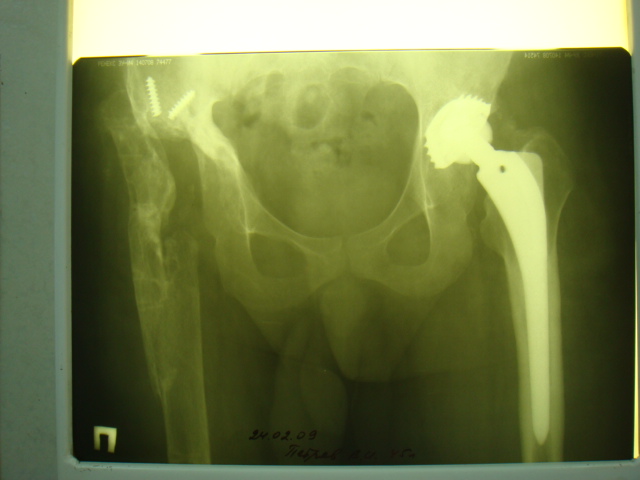

2005 г. при падении с высоты - перелом бедра в верхней трети, наложение АВФ . 3 года пациент ходил с аппаратом(рис. 3).

Обращение в нашу клинику в 2008 г. - демонтаж аппарата (рис. 4). Сегодня укорочение 8 см. Слева - протез стабилен, безболезнен.